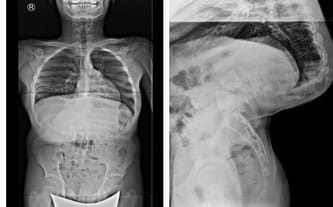

Witek urodził się z dużą skoliozą rotacyjną. To niestety niejedyny problem. Synek dodatkowo zmaga się z wadą zgryzu, wadą wzroku i licznymi wadami wymowy. I choć walczymy z całych sił, wciąż jesteśmy krok za wszystkimi chorobami....